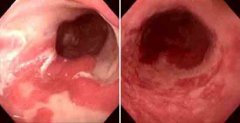

Barrett食管可以做哪些检查

导语 食管下段的鳞状上皮被柱状上皮覆盖,称Barrett食管,又称巴雷特食管。 查看更多